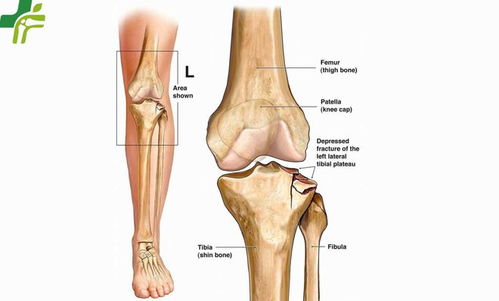

胫骨平台是位于胫骨上端的一个平台,与股骨的髁部形成膝关节。胫骨平台骨折是指胫骨平台部位发生的骨折,可能是由于直接撞击、跌倒或扭伤等原因引起。根据骨折的严重程度和位置,可分为多种类型,如单纯骨折、粉碎性骨折等。